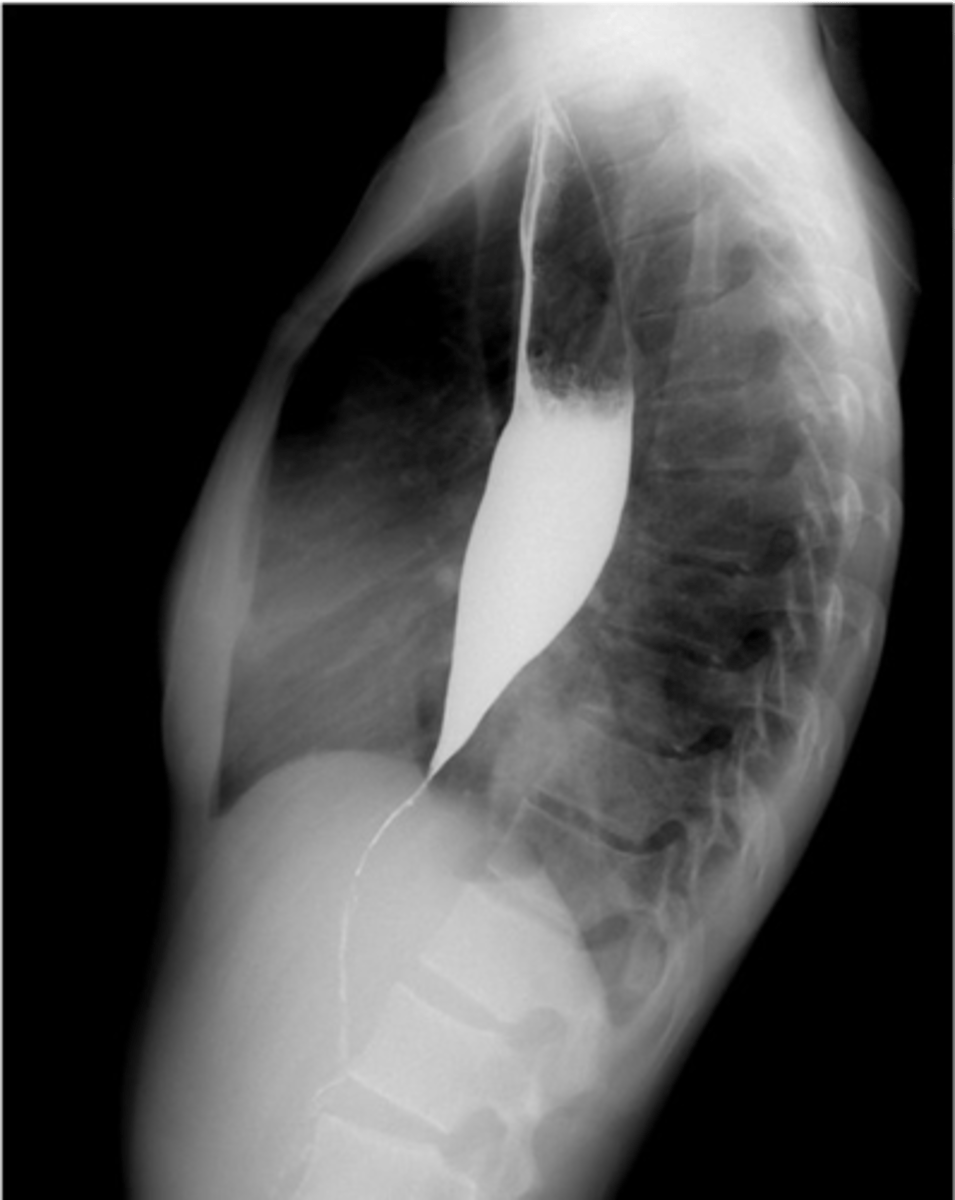

Achalasia

Achalasia (pic 5)

Achalasia (pic 2)

Achalasia (pic 3)

Achalasia (pic4 )